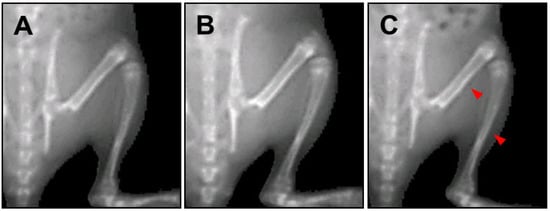

We used PIXImus to measure the femur and tibia length before sacrificing the rats, to serve as a skeletal growth marker (Figure 5). The femur length of the HT042-treated male and female groups was similar to control group. In comparison, a significant difference in femur length was observed in the rhGH-treated male and female groups (10.2% and 6.4%, respectively) compared to the control group. The tibia length of the HT042-treated male and female groups were similar to control group. In comparison, a significant difference in tibia length was observed the rhGH-treated male and female groups (7.5% and 5.7%, respectively) compared to the control group (Table 3).

Figure 5. Images of bone by PIXImus on spontaneous dwarf rats. The arrows indicate the area where bone length was measured in the femur and tibia. A: control group; B: recombinant human growth hormone (rhGH, 500 µg/kg, s.c.)-treated group; C: HT042 (100 mg/kg, p.o.)-treated group.

In this study, the lengths of the femur and tibia were not affected by HT042 administration to SDRs. The lengths of both the femur and tibia significantly increased in SDRs treated with rhGH compared to the control group. The femur length of the rhGH-treated group significantly increased by 10.2% (male) and 6.4% (female) compared to the control group. The tibia length of the rhGH-treated group significantly increased by 7.5% (male) and 5.7% (female) compared to the control group. Other studies on the SDR have reported an increase in bone length following GH treatment [15]. These results indicate that HT042 did not have a GH-like effect.